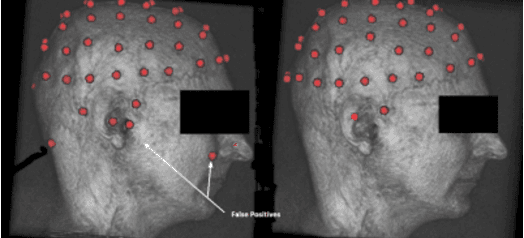

Abstract:Simultaneous EEG/fMRI acquisition allows to measure brain activity at high spatial-temporal resolution. The localisation of EEG sources depends on several parameters including the position of the electrodes on the scalp. The position of the MR electrodes during its acquisitions is obtained with the use of the UTE sequence allowing their visualisation. The retrieval of the electrodes consists in obtaining the volume where the electrodes are located by applying a sphere detection algorithm. We detect around 90% of electrodes for each subject, and our UTE-based electrode detection showed an average position error of 3.7mm for all subjects.